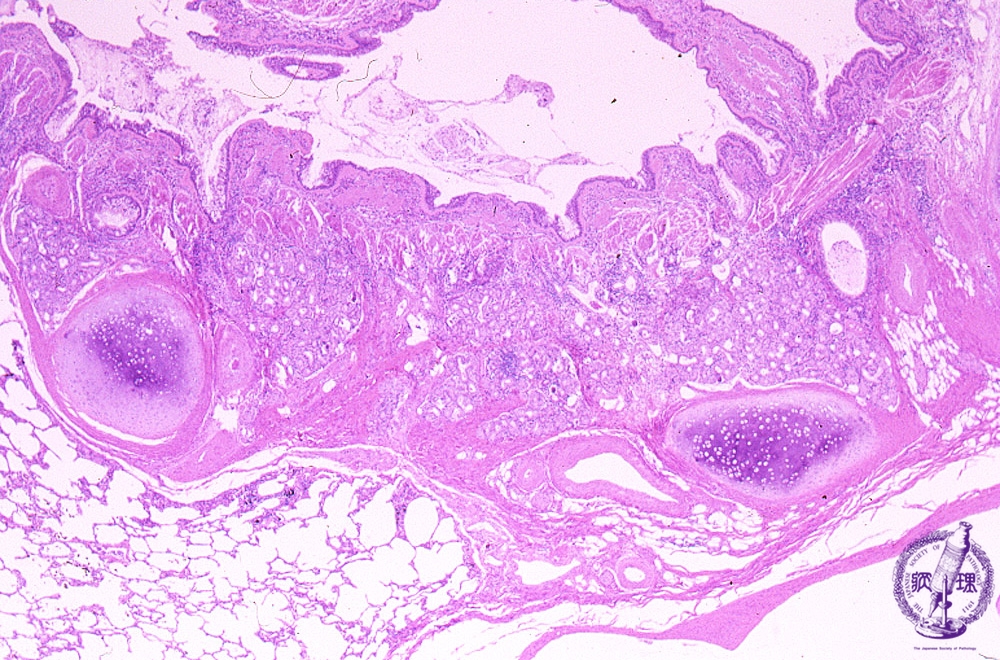

Microscopic view (HE stain, low power view): Bronchial glands are hyperplastic.

Click the image to see the enlarged image.